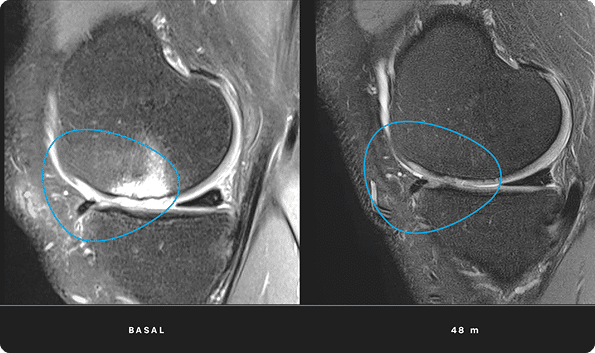

En ITRT hemos demostrado la viabilidad y seguridad de nuestras terapias mediante ensayos clínicos regulados y autorizados por la AEMPS (Agencia Española de Medicamentos y Productos Sanitarios). Una vez superado el ensayo clínico, la AEMPS autoriza el uso del medicamento en pacientes concretos, lo que permite ofrecer tratamientos personalizados con eficacia clínica y capacidad regenerativa demostrada.